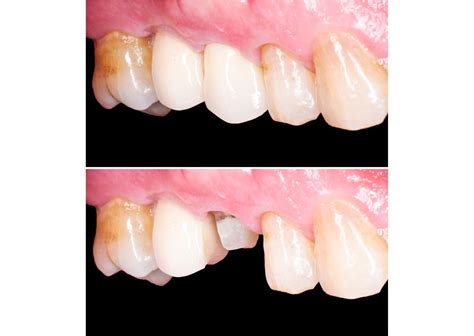

Antes de colocar la prótesis definitiva se evaluó el estado de salud y el volumen de los tejidos blandos periimplantarios conseguidos alrededor de la plataforma cónica del implante. Al año de la colocación, se observó el engrosamiento y estado de salud de los tejidos periimplantarios y una emergencia de la corona definitiva con respecto al tejido gingival circundante, imitando los dientes de la paciente, en ala de gaviota.

Al año de seguimiento, los tejidos blandos habían engrosado y se observó el buen resultado estético del caso clínico.

LA TÉCNICA DE CIRUGÍA GUIADA facilita obtener una emergencia protética correcta y, con ello, la obtención de unos resultados estéticos y biológicos óptimos, asegurando la estabilidad de los tejidos duros y blandos a largo plazo (D’haese y cols. 2017). En los implantes de una pieza con cuello pulido es especialmente importante el posicionamiento de la plataforma del implante con respecto al margen de la futura rehabilitación protética y el paralelismo entre los distintos implantes.

Un implante transgingival demasiado coronal puede tener consecuencias estéticas y protéticas muy graves. Con la aparición de los implantes de cuello convergente, además de tener mayor flexibilidad a la hora de colocar esta plataforma, se consigue mayor espacio para los tejidos blandos periimplantarios si se combina con una prótesis con un margen con diseño BOPT. El fin de esta técnica protética combinada con el diseño de los implantes de cuello convergente es decidir la posición del margen gingival modificando el perfil de emergencia de la restauración y dar más espacio a los tejidos blandos para conseguir su engrosamiento en un aspecto más coronal y mejorar la estabilidad a largo plazo (Canullo y cols. 2017; Canullo y cols. 2019).